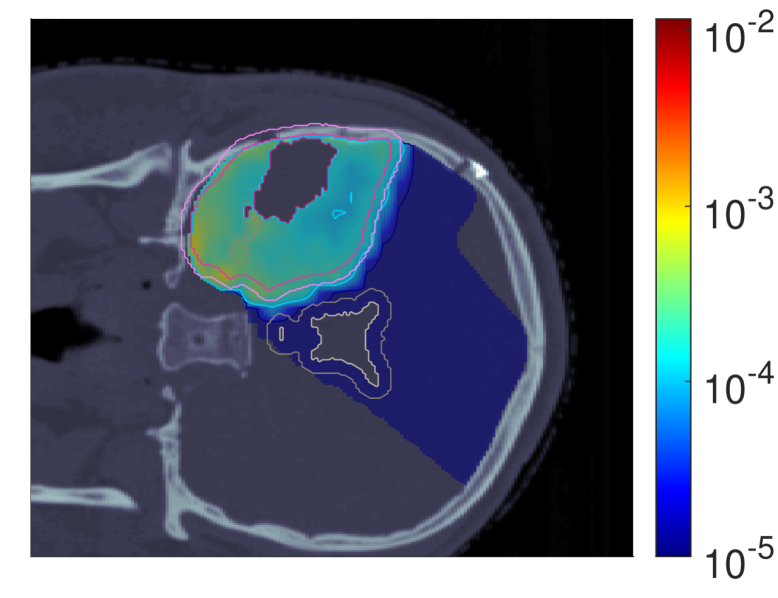

In light of the dose distribution changes and the interdependency between dose and dose-averaged LET, we can identify patterns in the slice images with the optimal dose-averaged LET distributions shown in Figure 5.

NTCP30 %NTCP\approx{$30\text{\,}\mathrm{\char 37\relax}$} NTCP20 %NTCP\approx{$20\text{\,}\mathrm{\char 37\relax}$} NTCP10 %NTCP\approx{$10\text{\,}\mathrm{\char 37\relax}$}

ldl_{d} (NTCPp)(NTCP_{p})

Refer to caption Refer to caption Refer to caption

ldl_{d} (LSEp~)(LSE_{\tilde{p}})

ldl_{d} (H~p)(\tilde{H}_{p})

ldl_{d} (H~p~)(\tilde{H}_{\tilde{p}})

Figure 5: Optimal slice images of the dose-averaged linear energy transfer ldl_{d} (in keV/μ\boldsymbol{\mu}m) for NTCPpNTCP_{p}, LSEp~LSE_{\tilde{p}}, H~p\tilde{H}_{p} and H~p~\tilde{H}_{\tilde{p}} at different NTCP levels. The shifts in ldl_{d} coincide with those observed on the slice images for dRBE,fxd_{RBE,fx}, i.e., there seems to be a trade-off between dRBE,fxd_{RBE,fx} and ldl_{d} that is consistent with the mathematical structure of the POLO model. As a result, the ldl_{d} slice images for NTCPpNTCP_{p} and H~p\tilde{H}_{p} are almost equivalent, while LSEp~LSE_{\tilde{p}} and H~p~\tilde{H}_{\tilde{p}} differ. For the latter two objective functions, the shift of dRBE,fxd_{RBE,fx} outside the target volume appears to be crucial, or, respectively, no shift of ldl_{d} is necessary due to the strength of the reduction of dRBE,fxd_{RBE,fx}.

First, we note that ldl_{d} hotspots do not manifest in the high dose regions – this would be a risk driver because of the product term in the POLO model from Section II.A. Generally, some trade-off between dRBE,fxd_{RBE,fx} and ldl_{d} is evident, where the optimizer allows for higher values of ldl_{d} when dRBE,fxd_{RBE,fx} has been sufficiently reduced, and vice versa.

For NTCPpNTCP_{p}, the slight reduction of dRBE,fxd_{RBE,fx} outside the target volume coincides with a redistribution of ldl_{d}: higher values in the target volume are prevented, and instead induced along the margins of the PTV. Once again, H~p\tilde{H}_{p} behaves almost identically. Following the dose/LET trade-off, the almost unchanged values for LSEp~LSE_{\tilde{p}} can also be explained: LSEp~LSE_{\tilde{p}} minimally reduces dRBE,fxd_{RBE,fx} in the region of overlap with the VS, meaning that high ldl_{d} values there would be detrimental to the outcome prediction. Consequently, ldl_{d} could only approach the “dose gap” that opens up within the target volume, or remain constant while the shifts in the dose distribution account for the reduction in NTCP.

Finally, for H~p~\tilde{H}_{\tilde{p}}, we observe a sharp envelopment of the lower side of the PTV margin, consistent with the fall-off in dRBE,fxd_{RBE,fx} there. At an NTCP level of 10 %10\text{\,}\mathrm{\char 37\relax}, the high ldl_{d} region has virtually manifested itself with hot spots partially overlapping the VS. However, revisiting the slice image for dRBE,fxd_{RBE,fx}, this is not surprising, as in addition to the lower values in the target volume, the dissipation of dRBE,fxd_{RBE,fx} to the outside is only enhanced towards the upper end, leaving space for the ldl_{d} band on the lower end, between the PTV margin and the VS.